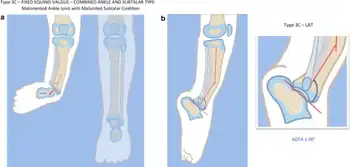

![]() | |

| a, b) Paley type 3c fibular hemimelia | |